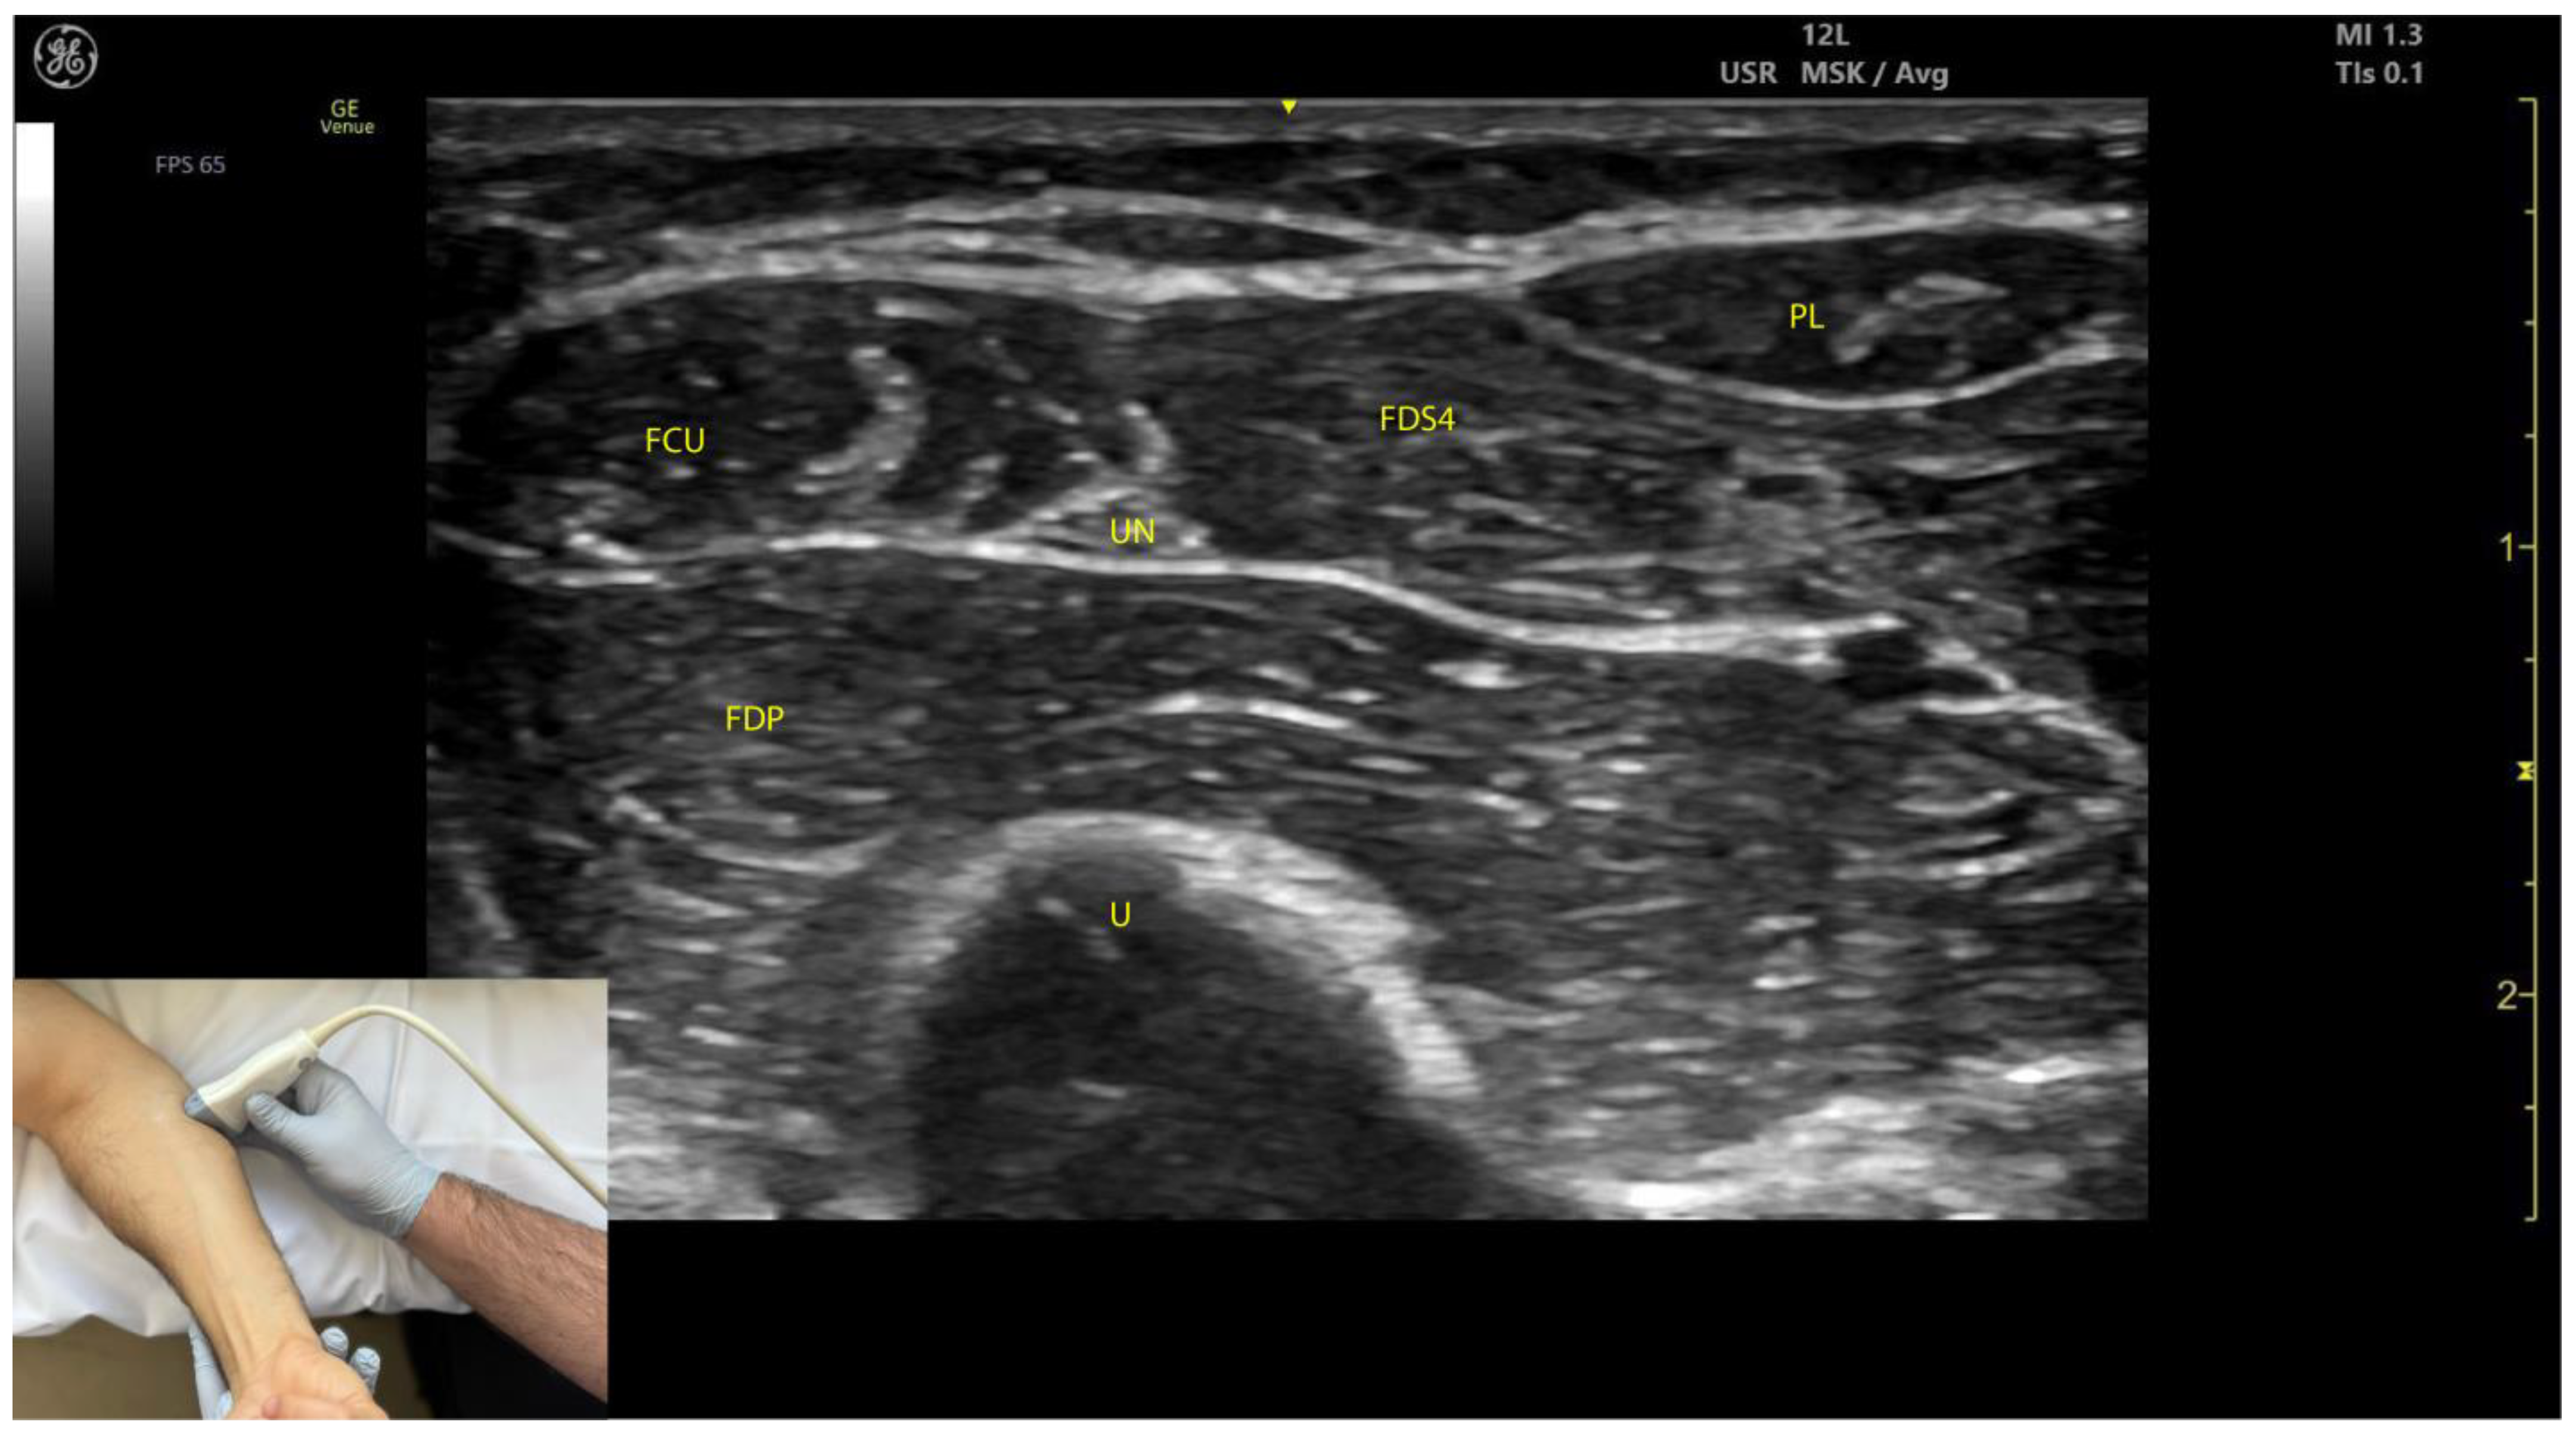

2.3.3. Key Ultrasound Landmarks (Figure 3)

- Muscle position: The FCU is the most medial muscle mass in the flexor compartment of the wrist, located on the volar aspect of the forearm [24].

- Internal fascia: The intramuscular fascia, often referred to as “cloud fascia” due to its cloud-like appearance, separates the humeral and ulnar heads of the FCU. This fascia can be visualized from the muscle’s origin at the medial epicondyle, extending distally until the FCU transitions into its tendon [23].

- Ulnar nerve (Video S2): The ulnar nerve is located deep to the FCU approximately 2–3 cm distal to the elbow crease. When scanning cranially toward the medial epicondyle, the ulnar nerve can be seen passing between the humeral and ulnar heads of the FCU as it enters the volar compartment of the forearm [25,26]. Scanning distally reveals a gradual decrease in FCU muscle size and an increase in FDP muscle size. At the mid-forearm level, the ulnar nerve joins the ulnar artery, and both structures descend together into the distal forearm toward Guyon’s canal [26].

- External fascia: The external fascia distinctly demarcates the FCU from adjacent muscle masses, facilitating precise BoNT-A injection.

- Dynamic evaluation: Contraction of the FCU is observed during wrist flexion and adduction maneuvers.